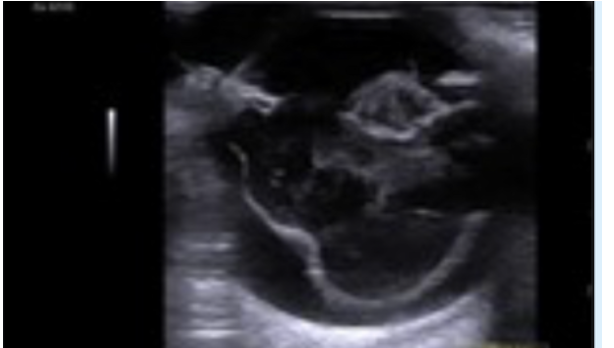

Ultraschall des linken Auges eines Patienten mit Diabetes Mellitus und einer bilateralen sekundären Katarakt (siehe Foto). Die Linse ist intumeszent (geschwollen) was welche schwere Komplikation zur Folge haben kann?

Welche der folgenden Anomalien kann auf dem Ultraschallbild dieses Hundes erkannt werden?